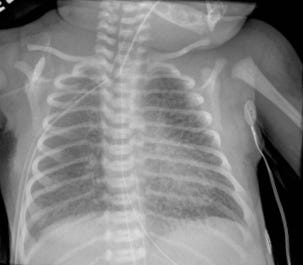

Above: A typical X-ray in an infant with PIE. Note the bubbly lucencies mostly in the left lung. The infant has a chest tube in on the right, so also had a pneumothorax, another type of air leak.